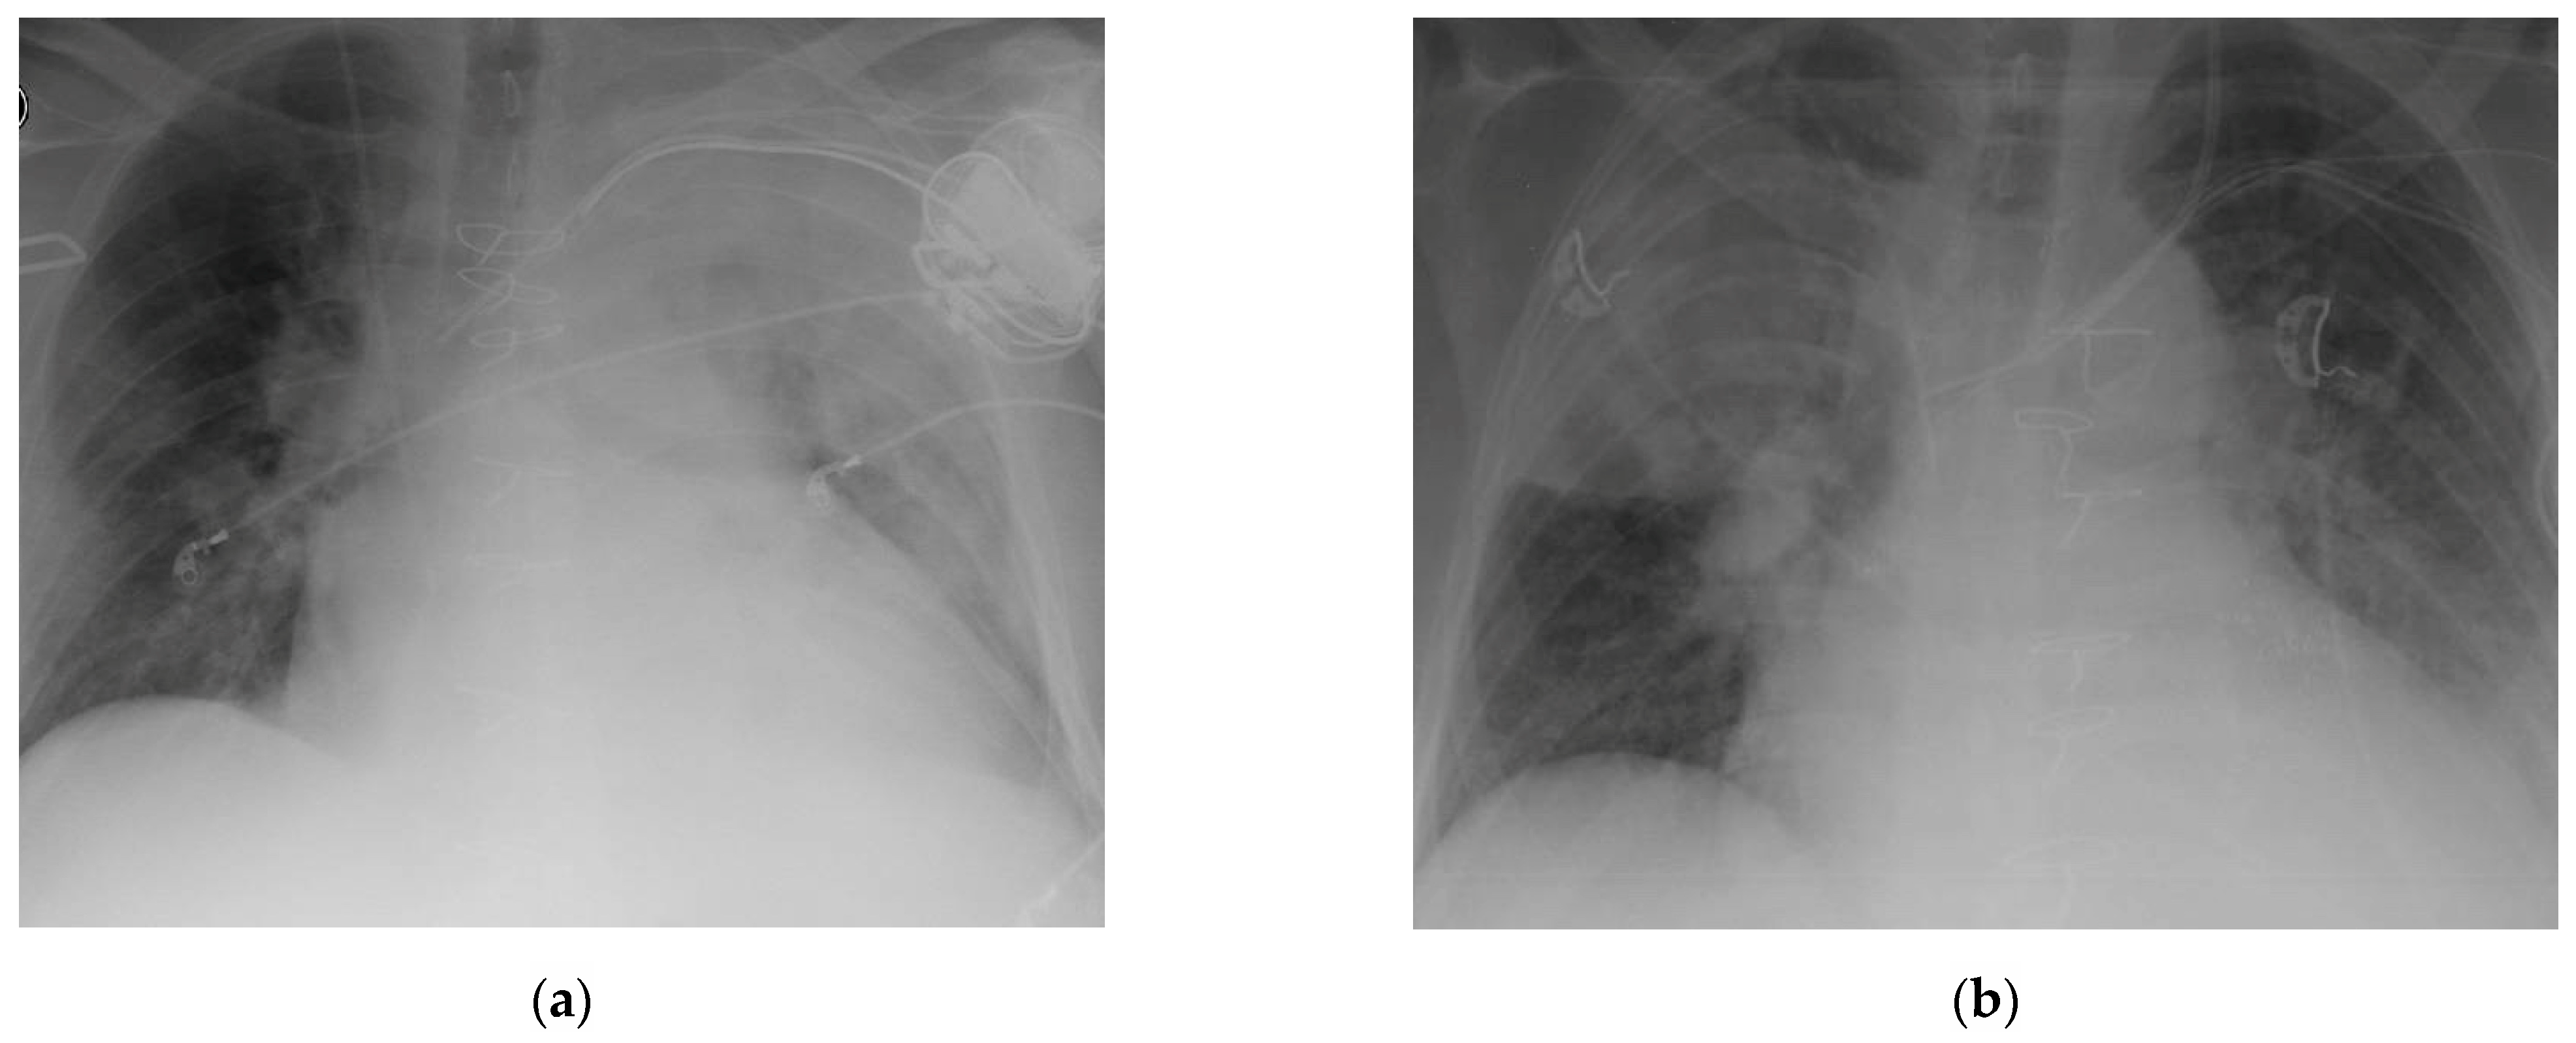

3.4. Laboratory Results, Clinical Symptoms and CT Scan Analysis

| CT scan: | |||

| Segment involved | 3.5 [2–7] | 2 [2–7.25] | 0.960 |

| Left lobe | 1.5 [1–4] | 2 [1.5–2.25] | 0.736 |

| Right lobe | 2.5 [2–3] | 2 [0–4.5] | 0.904 |

| Findings: | |||

| Consolidations | 6 | 2 | 0.464 |

| Nodules | 4 | 6 | |

| Small | 1 | 1 | 0.7469 |

| Large | 3 | 5 | 0.747 |

| Parabronchial infiltrate | 1 | 1 | 0.591 |

| Crescent sign | 3 | 4 | 0.067 |